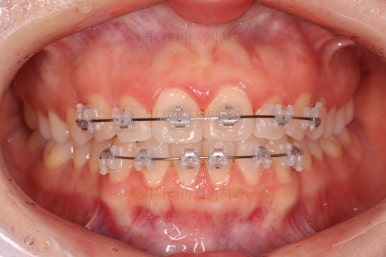

장치 부착 시점의 사진입니다.

장치를 붙이고 철사가 구불구불 들어가게 되면 그제서야 "이렇게 많이 틀어져 있었구나"를 더 잘 느 끼시게 됩니다.

이번에 사용한 장치는 엠파워 클리어라고 하는 자가결찰 세라믹 장치인데 같은 계열로는 엠파워 클리어를 비롯해 클리피씨 등이 있어요.

치아에 붙는 장치가 치아색과 비슷한 세라믹으로 만들어져 있고 철사를 붙잡아 주는 클립이 달려 있어 스스로 철사를 묶을 수 있다고 해서 "자가결차" 이라고 표현해요.

클리피씨 장치가 가장 유명하긴 하지만 매우 다양한 제품이 있고 거의 비슷한 장치이기 때문에 의사와 상의 하에 선택을 하시면 됩니다.

엠파워 장치는 미국, 클리피씨는 일본장치이며 기능적으로는 둘 다 우수한 장치입니다.